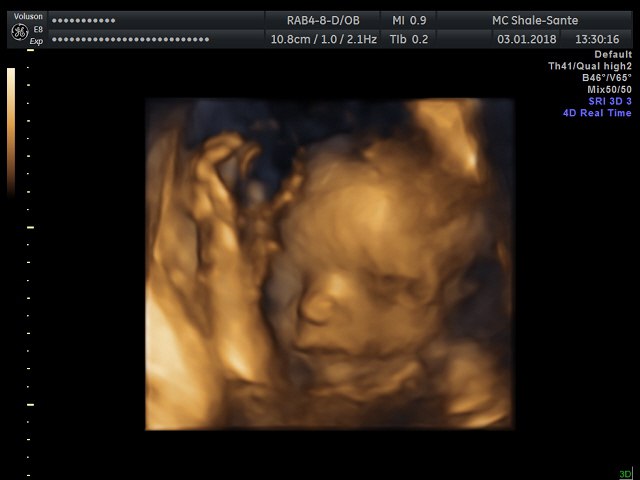

Нас померили,все все все посмотрели, все органы,врач про каждый рассказывала,притензий к нам нет, срок четко вообще совпадает пдр на 23 апреля)))

Весим уже 640гр,срок 24 недели и 3 дня. За 3 недели набрали 300 гр. Лежит косо,головой вверху,верится там как хочет))

На старшую вообще не похожа😂помоему вторая пошла в семью мужа,ну посмотрим. Но губы и нос явно не мои)))даж в профиль она другая,на сестру не похожа